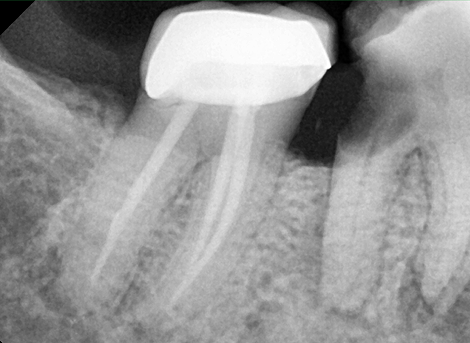

More Precise Cleaning

Complete disinfection of the root canal.

Cleaning & Filling

Sealing the Canal

Laser Cleaning